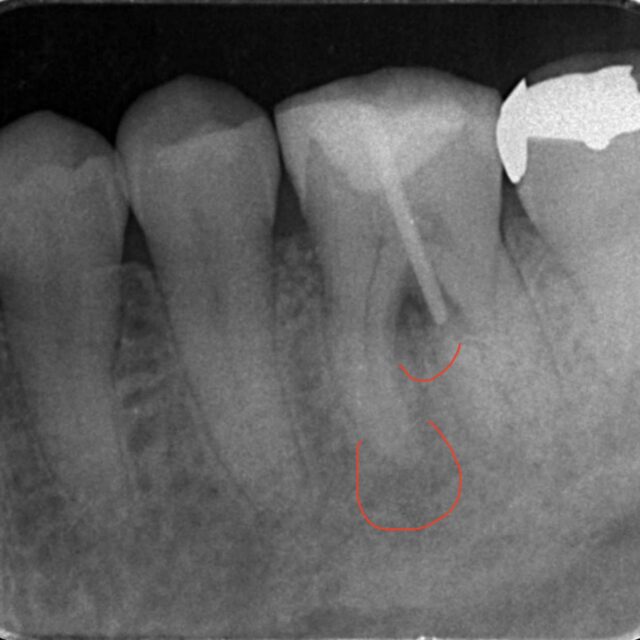

中心結節の破折からの根尖病変 2026/04/01 症例集 内容:下顎の小臼歯のMTA根管充填 治療費:12万円 治療期間:2回 主なリスク:術後の痛み 患者さんは10代の男性 歯茎がかなり腫れてきた。痛みが続く レントゲンは以前のもの 以前冷たいものが染みるということでレントゲンを撮影したが、中心結節が欠けたためと診断し、経過観察を行なっていた。 ところが… 続きを読む